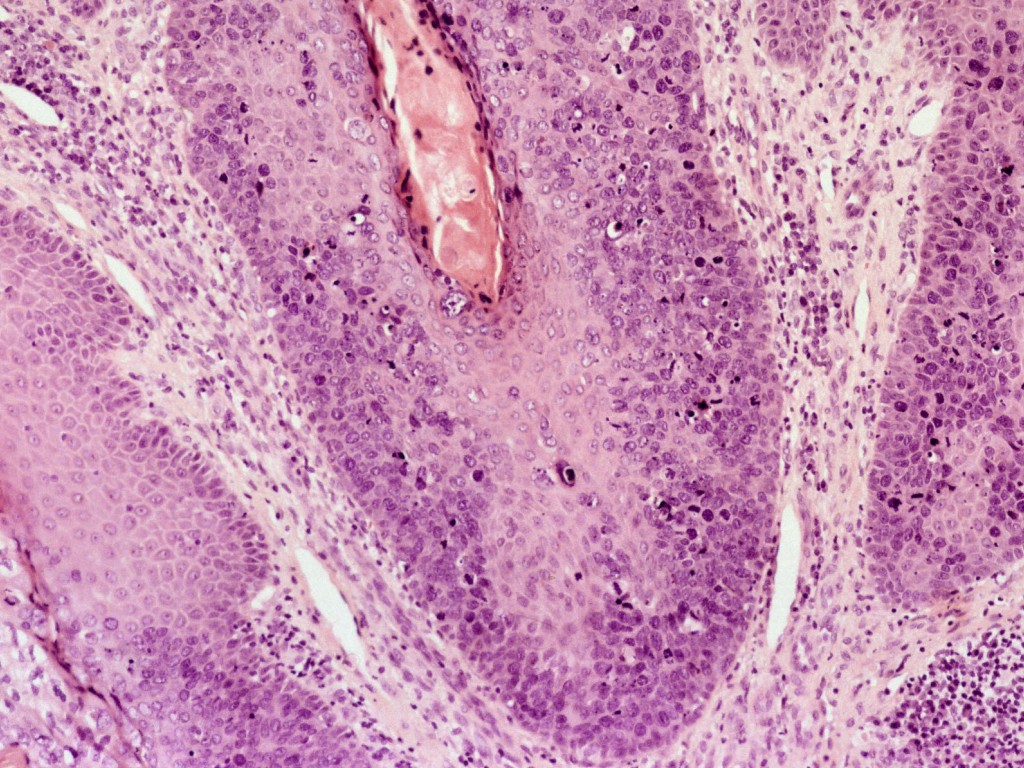

de urethra en blaas. Histologisch onderzoek is noodzakelijk om te differentiëren

van verruceus carcinoom en plaveiselcel-carcinoom. Bij Buschke-Löwenstein tumoren

blijft het stratum basale intact.

| Buschke-Löwenstein

(PA) |

Buschke-Löwenstein